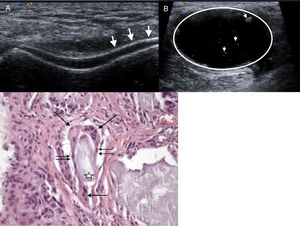

Clinical caseA 44-year-old male, attending hospital due to low back pain. One year earlier he experienced onset of progressive low back pain irradiating to the left pelvic limb. Six months earlier he presented sudden onset left knee arthritis, which remitted with anti-inflammatory drugs. The patient was hospitalised, physical examination found independent gait, guarding, claudication, decreased spinal mobility due to pain, positive Lasègue and Bragard, hypoaesthesia in L5-S1 dermatome, and RI with joint effusion. Blood biometry, urinalysis, erythrocyte sedimentation rate and C-reactive protein with normal parameters, serum uric acid of 11.8mg/dl and uric acid in 24h urine test: 560mg. X-ray with lytic spondylolisthesis of L5, on magnetic resonance imaging (MRI) hypointense signal in T1 and heterogeneous in T2 located in the L4-L5 interspinous space, and in the left facet joint invading the neuroforamen with bilateral lysis of the interarticular pars (Fig. 1). Ultrasound of the left knee showed “double contour” of the cartilage of the medial femoral condyle (Fig. 2A) and thick-walled Baker's cyst with hyperechoic stippling in its interior (Fig. 2B). Laminectomy, L5 radicular release, L5-S1 transpedicular fixation and postero-lateral arthrodesis. The histopathological study of the material removed by surgery reported amorphous amphophilic acellular material comprising epithelioid histiocytes fusing their cytoplasms together to form foreign body multinucleated giant cells (Fig. 2C).

(A) Double contour image of the femoral cartilage (arrows). (B) Thick-walled Baker's cyst (circle) with hyperechoic stippling in its interior (arrow heads). (C) Acellular amorphous amphiphilic material (star) bordered by epithelioid histiocytes (double arrow) and multinucleated giant cells (arrow) phagocyting this material.